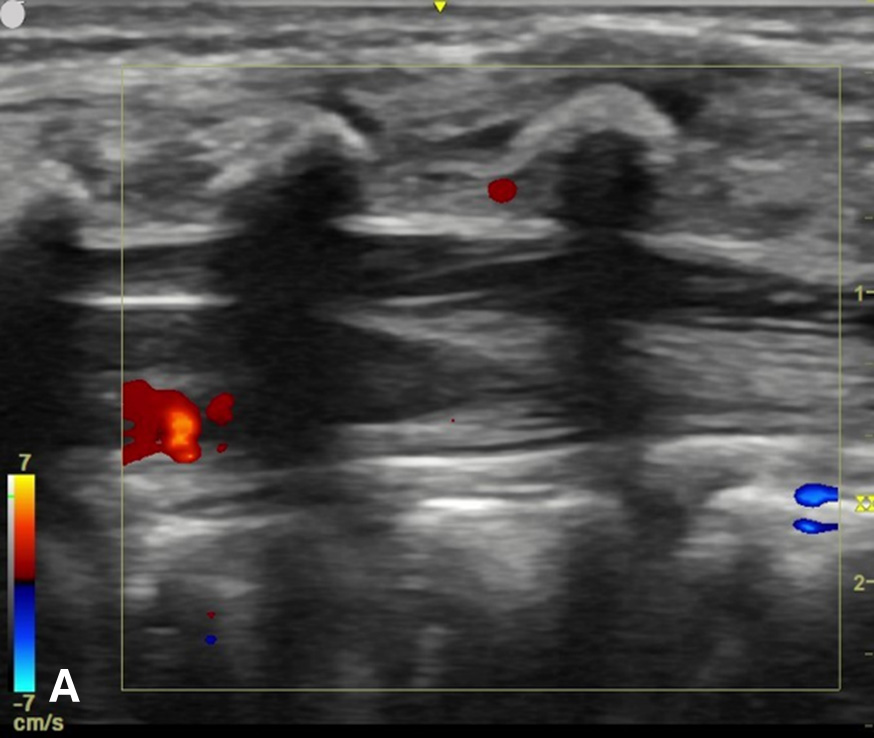

The transverse view should also be obtained to verify landmarks and identify any overlying vessels or hematomas (from prior attempts) to avoid. The transducer is rotated to the transverse position on the lower back and moved caudally over the spinous processes to locate the CM, which is a hypoechoic structure positioned in the center of the spinal canal. At higher levels of the CM, the ventral roots and dorsal roots can be identified, which are surrounded by the anechoic CSF. Next, gradually move the transducer caudally and observe the CM decreasing in size while being encircled by the hyperechoic fibers of the CE. (Figure 2) Once this sonographic landmark is identified, locate the center of the transducer and mark the corresponding area on the skin, aligning it with the center of the spinal cord. Subsequently, draw lines from both markers in both planes and utilize the point of intersection as a guide for inserting the LP needle. To enhance visualization of the spinal cord’s vascular supply, and avoid a space with any overlying vessels that may cause a traumatic tap, it is advisable to apply color Doppler in both the sagittal/longitudinal and transverse views.9 (Figure 3)

Figure 3 - Color Doppler US image of the spinal canal:

Figure 3A - The sagittal view demonstrates no prominent spinal vessels.